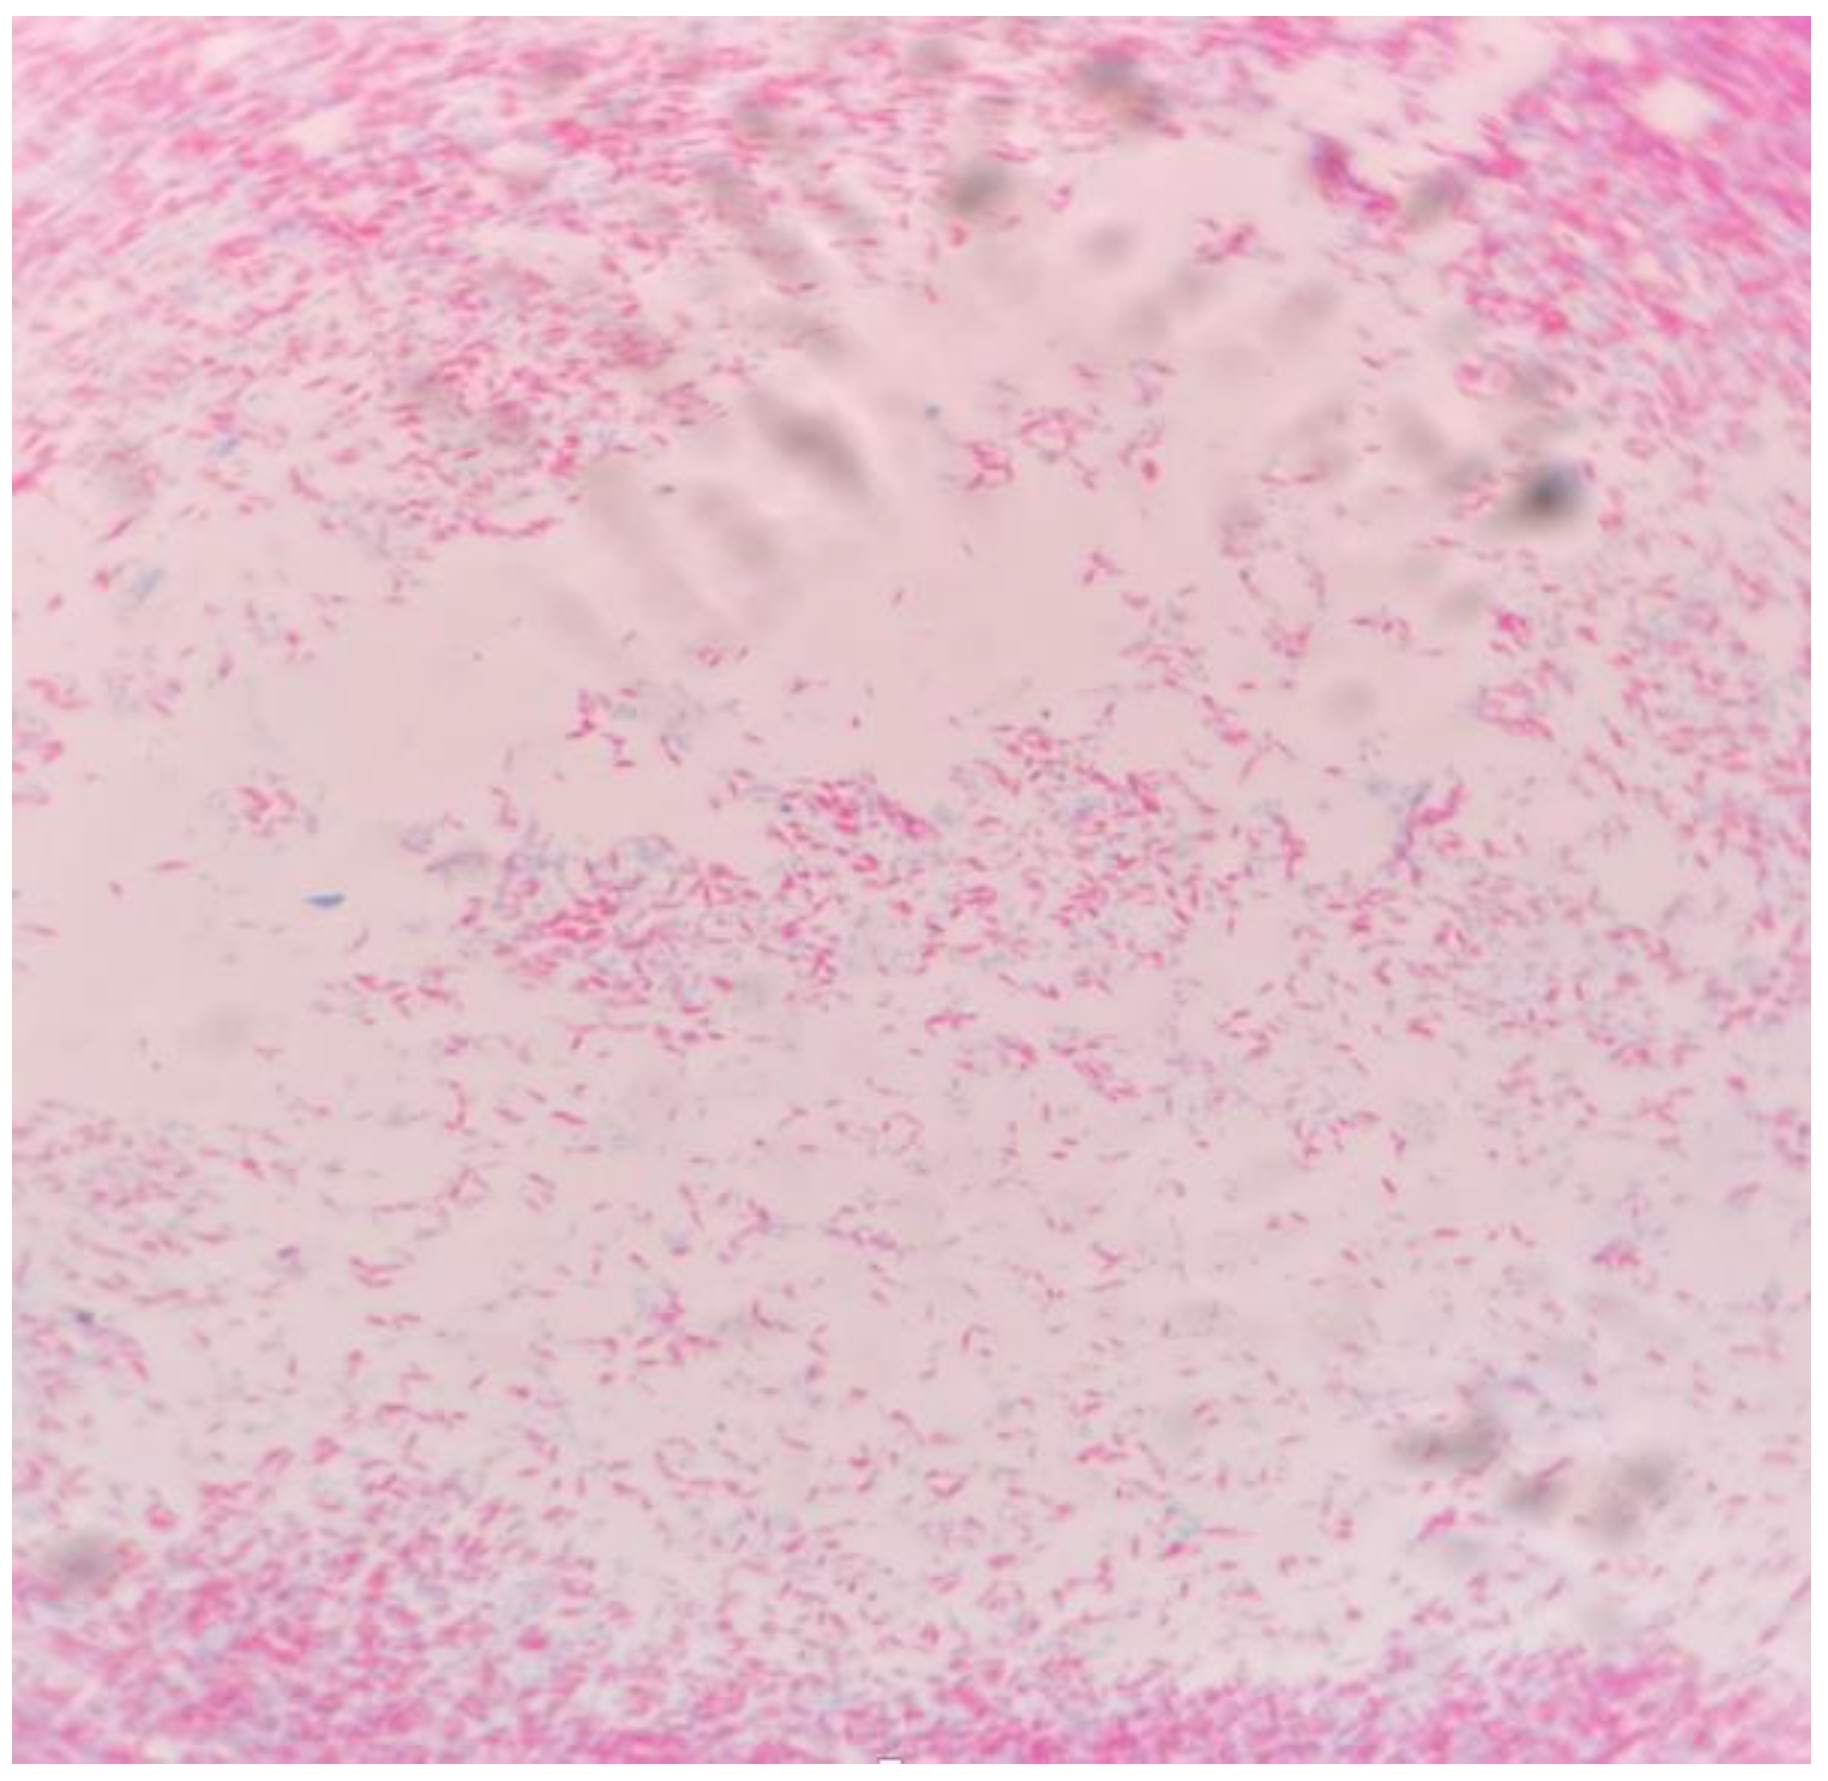

Case 1

Case 2

Case 3

Case 4